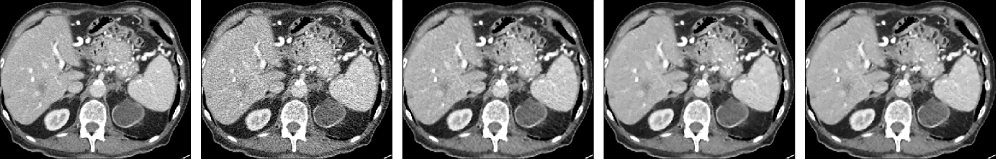

We show two source images and three restored images in Figs. 2(a)-(e) for visual comparison in global and local views. GUSL and CTformer stand out among the three benchmarks. GUSL can productively restore the LDCT images against image noise while effectively preserving the global structures and the local details of images.